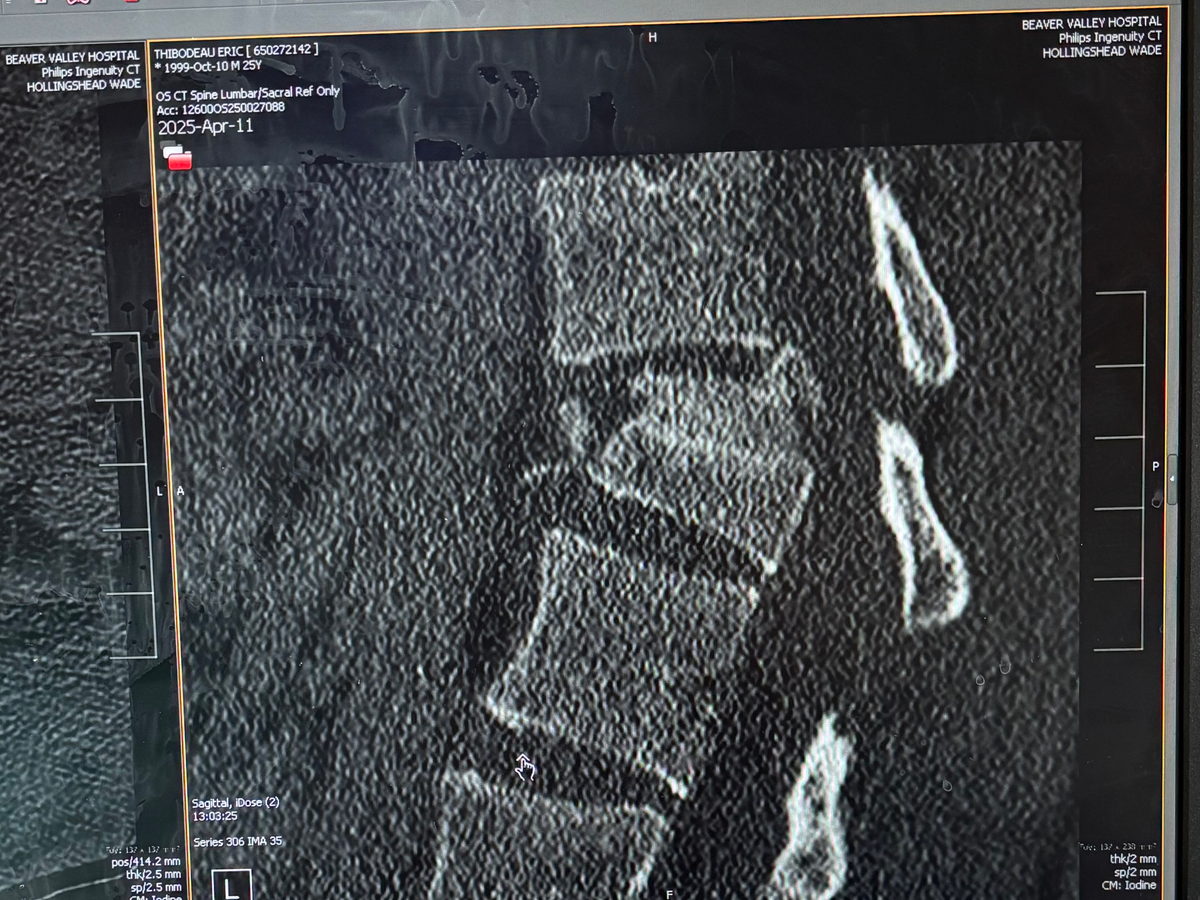

On Friday, my brother Eric was in a serious rollover crash while traveling through Utah with a friend. Thankfully, his friend—who sustained less severe injuries—has been discharged and is now recovering at home. Eric, however, was seriously hurt and underwent major back surgery. The procedure was urgent and intensive, and his road to recovery is just beginning.